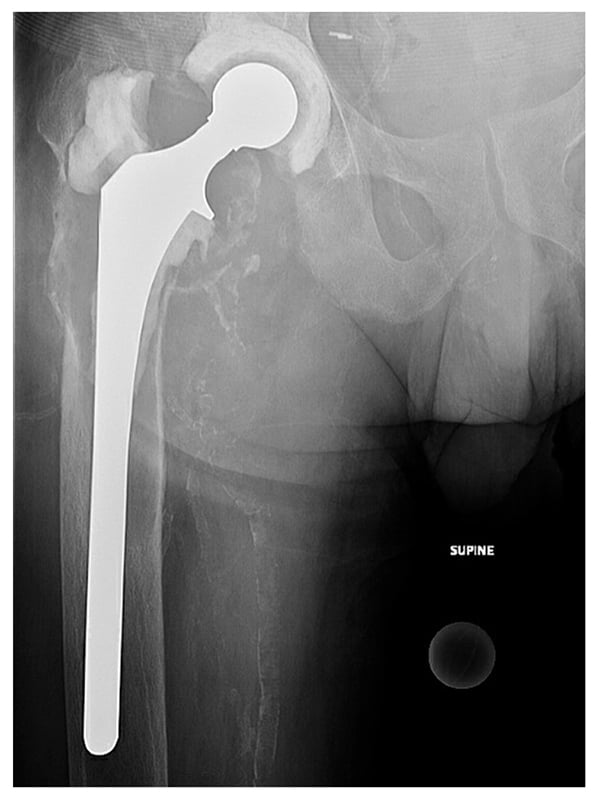

After a period of medical optimization, the patient underwent explantation, irrigation and debridement, and insertion of an articulating spacer. Despite proximal femoral bone loss, we preserved the proximal femur due to the patient’s young age and placed a 200-mm collared femoral component (Stryker Eon) coated proximally with antibiotic cement. We placed a semi-constrained polyethylene acetabular spacer component and used high-viscosity cement (Palacos R+G) containing gentamicin 0.5 g, vancomycin 2 g, and tobramycin 1.2 g per bag, with methylene blue incorporated (Fig. 2). Postoperatively, the patient was 20% weight-bearing on the leg with the foot flat and received a 6-week course of IV minocycline and levofloxacin. After a 2-week antibiotic holiday, repeat aspiration revealed concern for persistent periprosthetic joint infection (PJI), with a synovial white blood cell count of 4867 cells/μL with an 89% differential for neutrophils. The team had concerns that osteomyelitis was present in the proximal femur and that resection would be required.

Figure 2: Postoperative radiograph shows an articulating hip spacer with a semi-constrained acetabular component and long femoral component coated proximally with antibiotic cement.